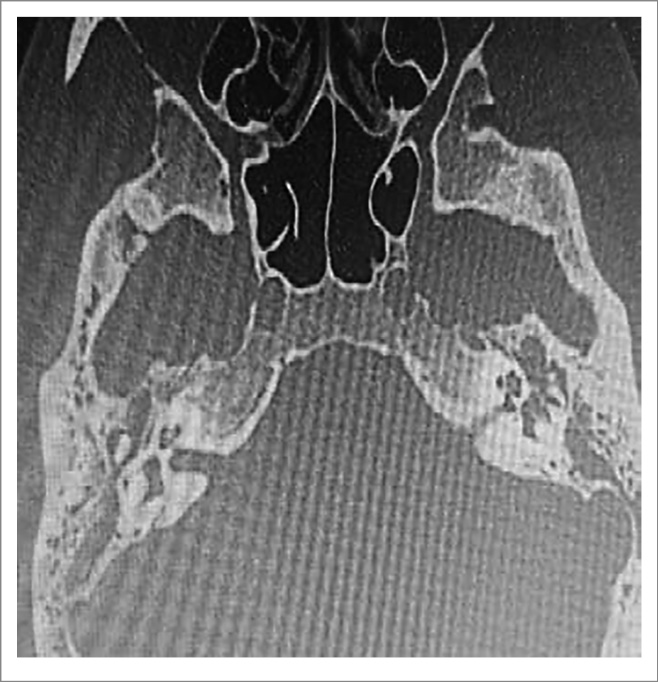

По данным мультиспиральной компьютерной томографии (МСКТ) височных костей с обеих сторон визуализировалось тотальное затемнение полостей среднего уха без деструктивных изменений, цепь слуховых косточек сохранна, прослеживается на всем протяжении (рис. 4, 5).

Рис. 4. КТ, аксиальный срез: тотальное затемнение полостей среднего уха без деструктивных изменений, цепь слуховых косточек сохранна, прослеживается на всем протяжении.

Рис. 5. КТ, аксиальный срез, правая височная кость: тотальное затемнение полостей среднего уха без деструктивных изменений, цепь слуховых косточек сохранна, прослеживается на всем протяжении.